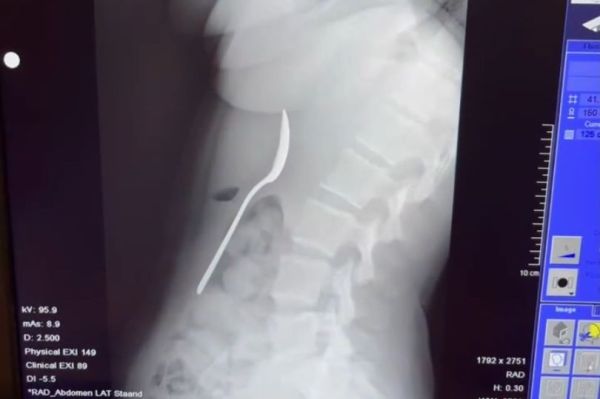

A young woman has revealed the "truly terrifying" moment she accidentally swallowed a 17cm-long spoon while eating yoghurt.

She said: " I didn't feel bad at all – so I didn't say anything about it right away. It wasn't until after dinner that I realised it was actually quite serious. There was a 17cm spoon in my stomach. Online, everywhere said the same thing: go straight to the emergency room. It was only then that I realised how dangerous it could be."

Doctors told her the spoon was too large to pass naturally, so she had to return home and wait until a gastroscopy could be scheduled. Reymy said: "That night was difficult, I felt the spoon moving, sometimes even between my ribs. It was truly terrifying.

The utensil was removed two days later under local anaesthetic. She added: "I wasn’t allowed to swallow while they pulled it up. They had to rotate it in my stomach, which caused a small gastric haemorrhage. It wasn't pleasant, but I felt pure relief when it came out."